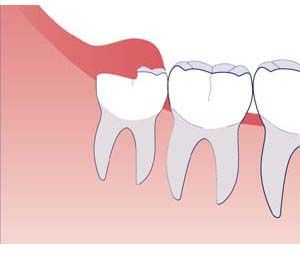

Wisdom teeth are the last teeth to erupt within the mouth. When they align properly and gum tissue is healthy, wisdom teeth do not have to be removed. Unfortunately, this does not generally happen. The extraction of wisdom teeth is necessary when they are prevented from properly erupting within the mouth. They may grow sideways, partially emerge from the gum and even remain trapped beneath the gum and bone. Impacted teeth can take many positions in the bone as they attempt to find a pathway that will allow them to erupt successfully.

These poorly positioned impacted teeth can cause many problems. When they are partially erupted, the opening around the tooth allows bacteria to grow and will eventually cause an infection. The result: swelling, stiffness, pain and illness. The pressure from the erupting wisdom tooth may move other teeth and disrupt the orthodontic or natural alignment of teeth. The most serious problem occurs when tumors or cysts form around the impacted wisdom tooth, resulting in the destruction of the jawbone and healthy teeth. Removal of the offending impacted tooth or teeth usually resolves these problems. Early removal is recommended to avoid such future problems and to decrease the surgical risk involved with the procedure.